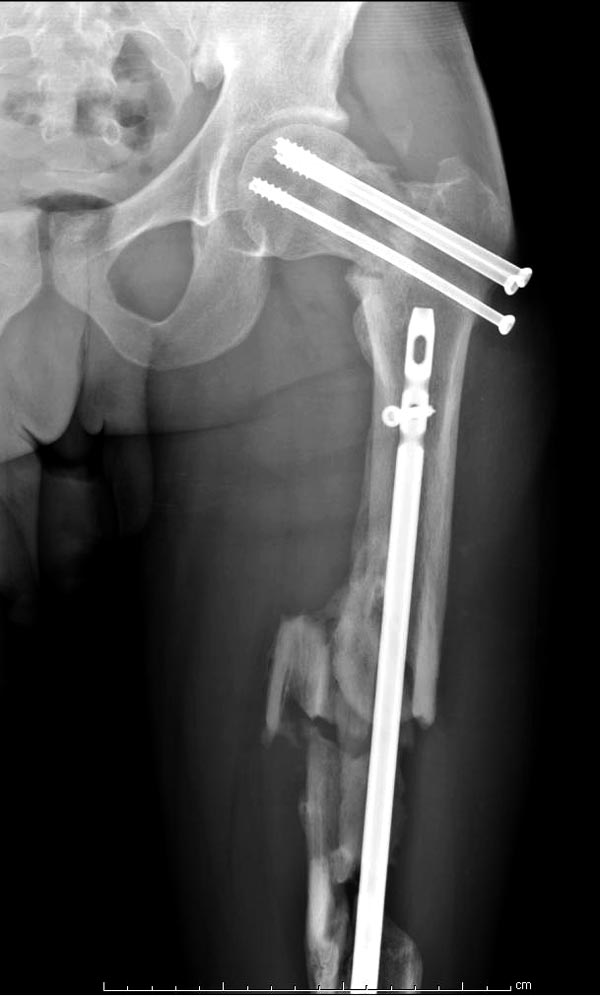

Здесь выставлен ренгенограммы больного, ему 21, травму получил в

результате высокоскоростной погони на украденной машине, которая

закончилась смертью трех остальных“боевых комрадов”. Начатую коллегой

открытую операцию на шейке пришлось закончить мне, установкой винтов и

ретроградной фиксацией бедра. Выписка в обычное сроки и наблюдался

амбулаторно. Каждый раз напоминали о возможности осложнений ввиде

несращения! По истечению 4 месяцев появились признаки варусной

деформации. На СТ срезах несращение шейки и бедра. Риминг, замена на

более толстый гвоздь и вальгусная остеотомия.